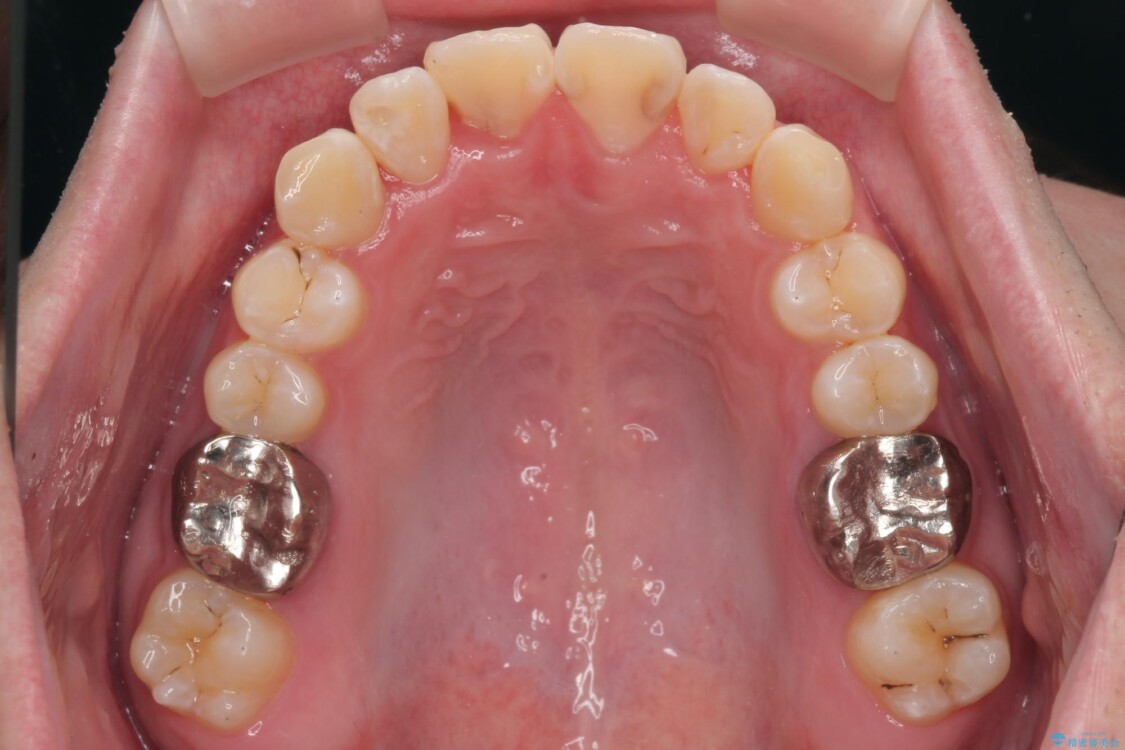

初診時の状態

・上下ともに歯がきれいに並びきらず、がたつきが見られました。

・上下の前歯の中心(正中)がずれています。

・特に上顎の幅が狭いため、下顎の歯列も内側に入り込み、歯が並ぶスペースが不足していました。

治療前

• 1年でここまで変わる!歯列のがたつきと正中のズレを改善した矯正治療(メタルブラケット×MARPE) 治療前画像